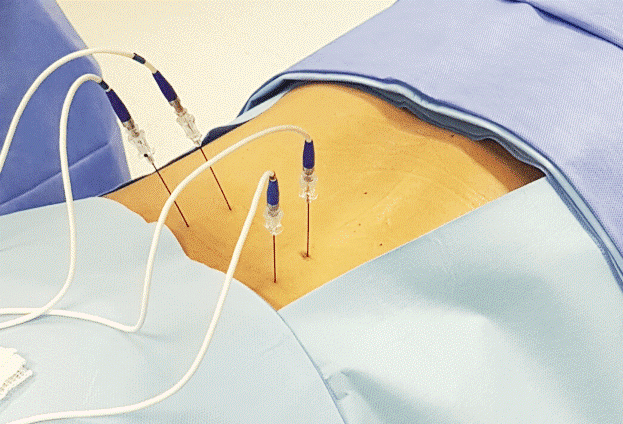

Tratamento da Dor

Dor aguda x Dor crônica

De forma geral, existem duas categorias de dor: a dor aguda e dor crônica. Ambas podem se manifestar de forma leve, moderada ou severa e sua etiologia é variada : dor neuropática, nociceptiva, nociplástica, mista... A dor crônica é aquela que tem duração superior a três meses. Existem diversas abordagens possíveis.

Prezamos por um abordagem cuidadosa, combinada a técnicas modernas que proporcionam mais qualidade de vida ao paciente.